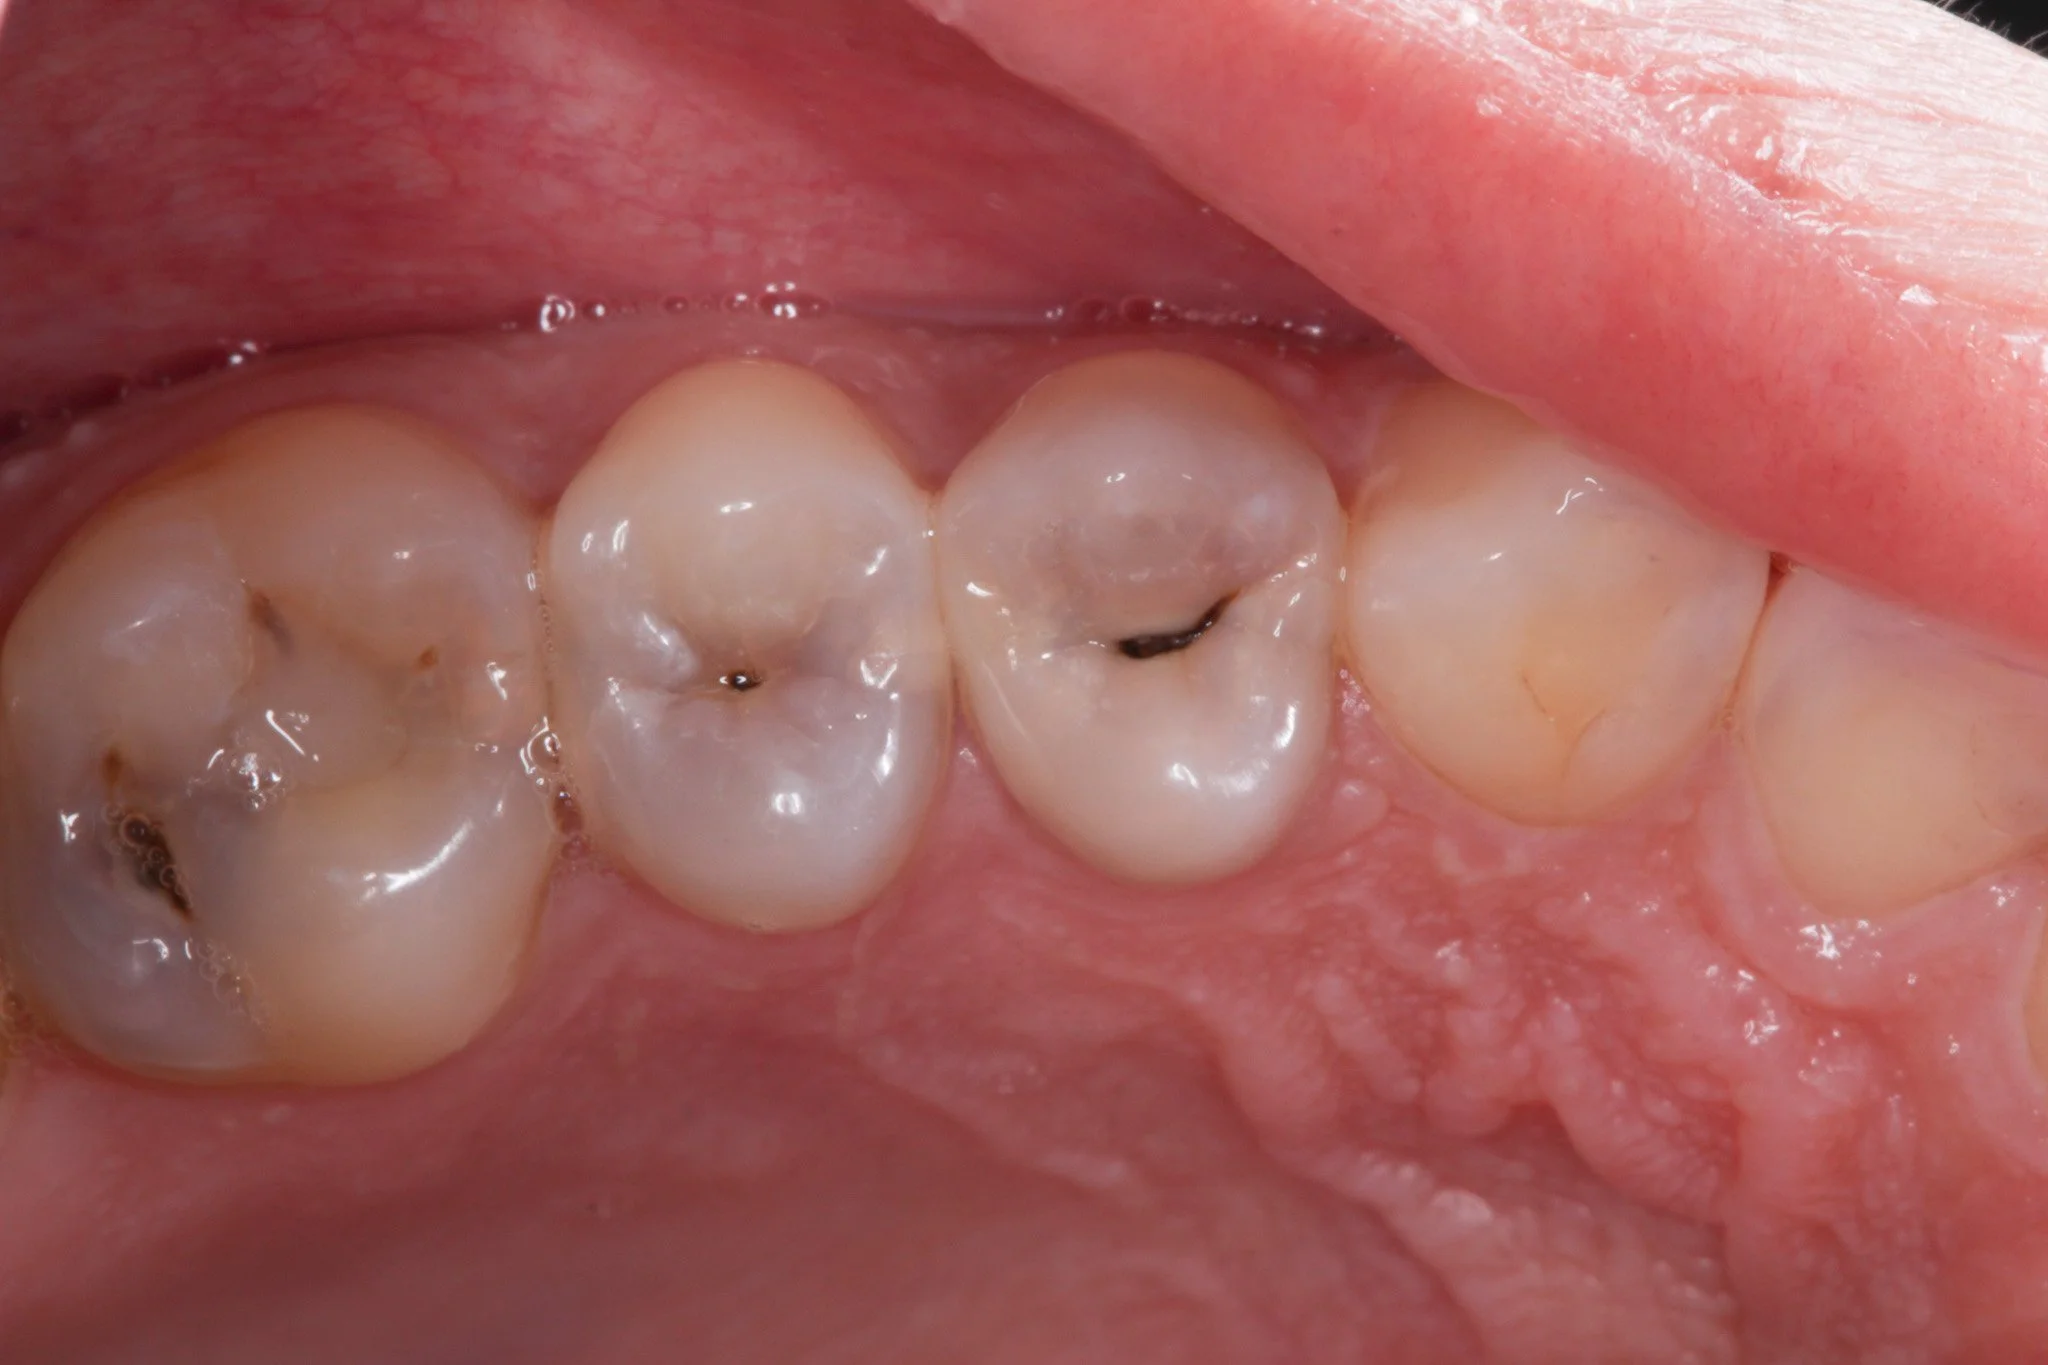

A tooth with decay

• Leaking margins - This is less visible but just as important. The edge where the filling meets the tooth can open slightly over time, allowing bacteria to seep in.

• Debonding - This is when the filling loses its seal and starts to separate from the tooth. It may still look intact, but the bond underneath has failed, creating space for bacteria to enter and potentially cause decay.

There is a gap at the amrgin where the fillings meets the tooth, allowing bacteria to gather and decay the tooth underneath